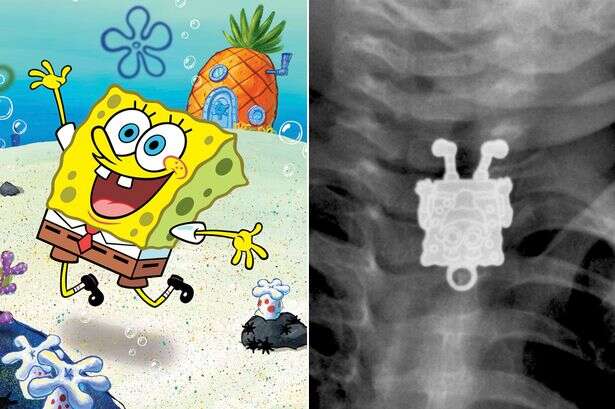

As imagens que você verá a seguir mostram exames de raio-X que são um tanto quanto incomuns.

Os exames mostram objetos pra lá de inusitados inseridos dentro dos corpos de pacientes de várias partes do mundo.

Todos eles certamente farão você estremecer de dor.

Os pacientes certamente tentaram usar tais itens para se dar prazer íntimo, mas acabaram se dando muito mal.